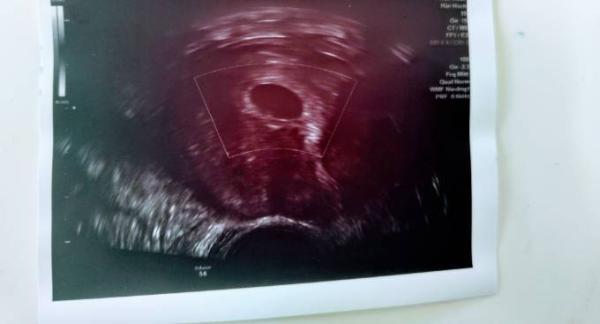

Guten Morgen leider hatte ich am Mittwoch die gleiche Situation war beim gyn an 5+3 und man sah nur eine leere fruchthöhle man macht sich solche Gedanken und Sorgen verstehe dich voll und ganz ich hänge dir Mal mein Bild an lass uns einfach hoffen das alles gut wird

Bild zu

Hallo liebe Lana, gut, bei dir sieht man zumindest eine ganz schöne Fruchthöhle...die sah man bei mir gar nicht so :) Ich denke dein Babylein hat sich versteckt oder ist noch ganz Mini .... Ich drück dir die Daumen, dass es positiv weiter geht - für uns beide - für alle!! Das warten bis nächste Woche zieht sich nun wie Kaugummi Du kannst mich/uns ja gerne auf dem Laufenden halten....wann musst du wieder zur Kontrolle? LG Evelyn